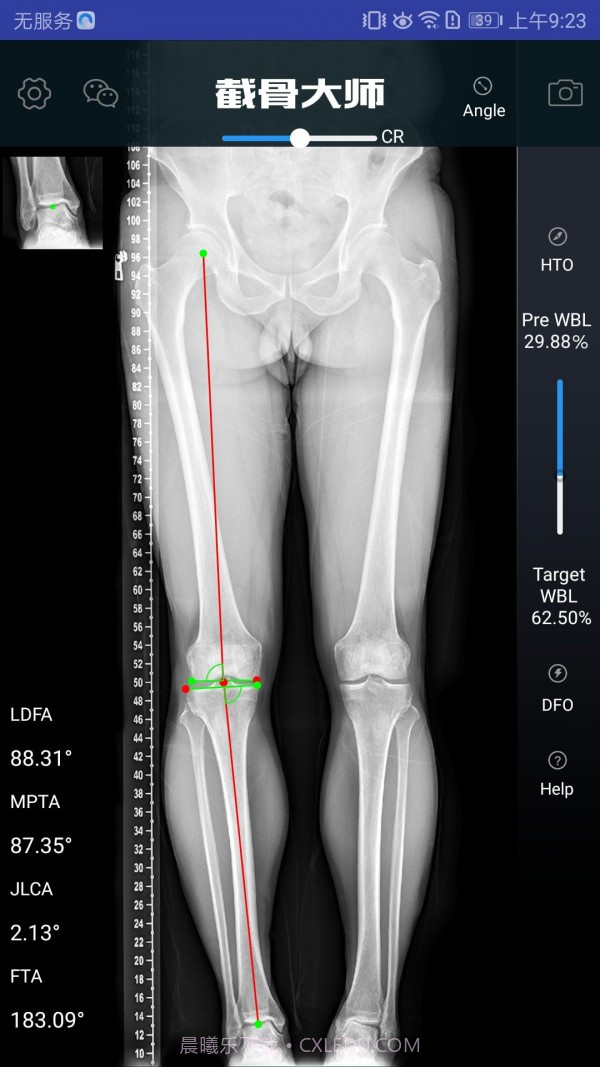

截骨大师真的是个宝藏APP,特别适合骨科医生和医疗人员使用。它的手术模拟功能超级高效,能让医生在手术前清晰地了解手术效果,避免在实际操作中出现失误。而且,它的参数计算非常精准,真的是为医生的工作提供了很大的帮助。用这款软件,你不仅能节省大量准备时间,还能显著提高手术的成功率,对患者的治疗也有很大保障。作为医生,这款工具简直是必不可少的选择!

精准的参数计算,避免手术中的失误

高效的手术模拟功能,医生可以直观了解手术效果

精准的算法支持,确保每个计算结果都可靠